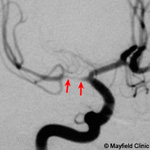

- Intracranial artery stenosis

Intracranial stenosis is a narrowing of an artery inside the brain. A buildup of plaque (atherosclerosis) inside the artery wall reduces blood flow to the brain. Atherosclerosis that is severe enough to cause symptoms carries a high risk of stroke and can lead to brain damage and death. Treatments aim to reduce the risk of stroke by controlling or removing plaque buildup and by preventing blood clots.